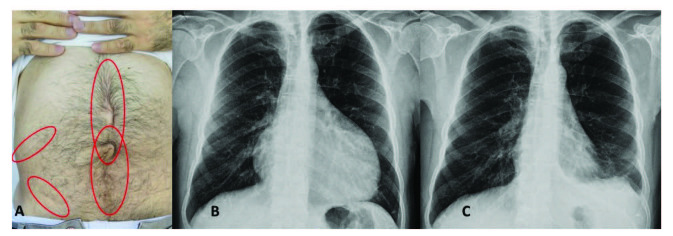

腹膜發(fā)作開始局限并迅速蔓延至整個(gè)腹部。腹膜炎癥會(huì)導(dǎo)致典型的腸梗阻癥狀,患者會(huì)遭受嚴(yán)重的胃痛。體格檢查顯示腹部肌肉僵硬、反跳痛和腸鳴音消失——臨床上這種緊急情況與急腹癥的手術(shù)原因無(wú)法區(qū)分。因此,隱匿性腹部手術(shù)史在良性陣發(fā)性腹膜炎患者中很常見(圖 1A)。在疑似病例中,影像學(xué)檢查可能有助于排除手術(shù)病理。腹部發(fā)作后可能會(huì)出現(xiàn)輕度反彈性腹瀉。盡管有戲劇性的表現(xiàn),但腹膜炎的所有體征和癥狀在 24-72 小時(shí)內(nèi)有效消退,沒有后遺癥,盡管慢性腹水和腹膜粘連的報(bào)道很少。

包含圖片、插圖等的外部文件。對(duì)象名稱為 turkjmedsci-50-1591-fig001.jpg

圖1:(A) 一位因多次腹部手術(shù)而留下疤痕的患者,(B) 胸部 X 光片顯示大量心包積液,(C) 同一患者用阿那白滯素治療后的胸部 X 光片。

心包炎是一種罕見病癥,見于 1%–2% 的患者。心包炎會(huì)出現(xiàn)胸骨后胸痛和呼吸困難等癥狀。心包填塞可能很少發(fā)生。心電圖顯示 ST 段抬高,胸部 X 光片可能顯示心臟輪廓的短暫擴(kuò)大(圖 1B 和 1C),超聲心動(dòng)圖顯示心包積液。在極少數(shù)情況下,反復(fù)性心包炎可能是良性陣發(fā)性腹膜炎的少有表現(xiàn),這可能與特發(fā)性心包炎相混淆 。